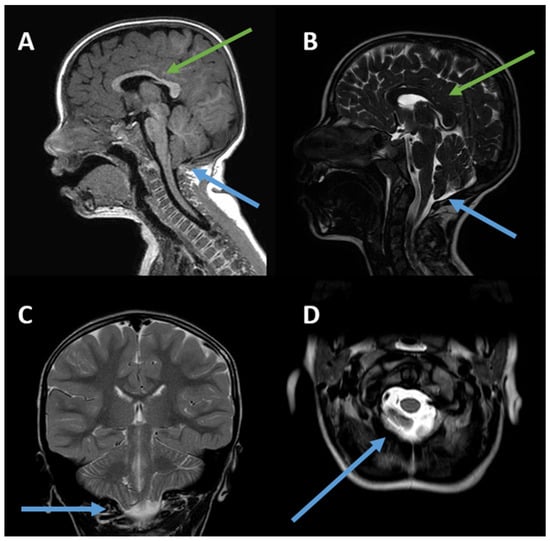

He was hospitalized again at the age of 6 years for motor impairment, sialorrhea, oral dyspraxia, and upper-limb tremors, which were reported since the age of 4 years. At this time, a second brain MRI confirmed ectopia of the cerebellar tonsils in the retro-medial cerebrospinal fluid space and through the foramen magnum, consistent with Chiari type I malformation, and reported a slight deviation of the optic chiasm, downward and to the right (Figure 1). The patient was discharged with a diagnosis of ataxia and a speech articulation disorder, as well as ectopia of the cerebellar tonsils (6 mm).

Figure 1. (AD). Chiari I malformation and slightly thinned appearance of the body/splenion junction of the corpus callosum. (A) Sagittal 3D TFE T1-weighted image; (B) sagittal T2-weighted image; (C) coronal T2-weighted image; (D) axial T2-weighted image. The green arrows indicate thinning of the corpus callosum, while the blue arrows refer to Chiari I malformation. The posterior fossa is small. The peg-like cerebellar tonsils (C) herniate into the foramen magnum (D). Tonsillar ectopia is more pronounced on the right (C). The axial image shows the tonsils (D) behind the medulla oblongata, which cause crowding of the foramen magnum.

Neuroimaging examinations in our patient revealed a Chiari type I malformation with descent of the cerebellar tonsils in all proposed projections. The descent of the cerebellar tonsils by 6 mm meets the minimum criterion for the diagnosis of type 1 Chari syndrome [20,21]. There are no other reported cases of Chiari I malformations in TCF20-NDD. However, the TCF20 gene is homologous to the RAI1 gene [5,9] which is associated with Smith–Magenis syndrome (SMS), a condition that may include posterior cranial fossa alterations [22]. Specifically, one SMS patient was described as having a small brain stem and vermis, as well as a mega cisterna magna in the posterior fossa. Neuroimaging examinations in our patient revealed thinning of the corpus callosum, in disagreement with a case series proposed by Schneeweiss et al. in 2022 [23], in which two adolescents with a thickened corpus callosum were described. In fact, the TCF20 gene may be indirectly involved in neuronal migration processes, as well as the development of the corpus callosum. In 2022, Zhou et al. [7] described a strong interaction between TCF20 and MeCP2 in the development of brain structures, highlighting its fundamental interactive role in preventing morphological alterations. Indeed, the MECP2 gene plays a role in the development of the corpus callosum, influencing its hypoplasia. This has been demonstrated in both animal and human models using voxel-based morphometry and tract-based spatial statistics [24,25].

In Chiari type I malformation, as described in the literature, ataxia-like symptoms are typically due to direct compression of the cerebellar vermis and hemispheres [28,29,30,31]. In light of this, it is unlikely that the upper-limb tremors, motor impairment, and walking difficulties reported in our patient are due to a direct effect of Chiari malformation. In particular, there were no evident signs of compression of the brainstem or upper spinal cord (Figure 1). To clarify the picture described above, we have added a table to the Supplementary Materials (Table S1) showing the symptoms associated with Chiari malformation.